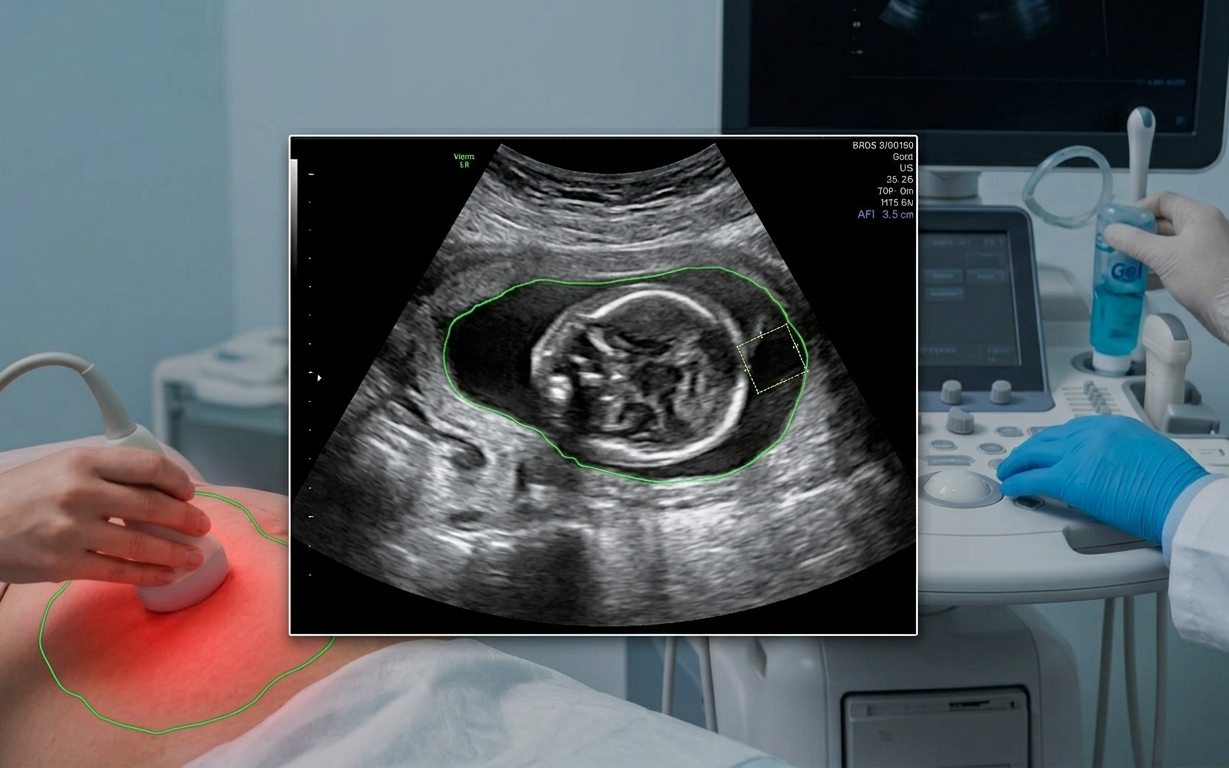

Các bác sĩ sẽ giám sát chặt chẽ sức khỏe tim mạch trong các buổi khám thai định kỳ.

Những điều chỉnh này là thiết yếu cho một thai kỳ khỏe mạnh nhưng việc theo dõi là rất quan trọng. Các bác sĩ sẽ giám sát chặt chẽ các chỉ số tim mạch trong các buổi khám thai định kỳ, cho dù mẹ bầu có bệnh lý tim mạch tiềm ẩn hay có nguy cơ gặp các vấn đề tim mạch liên quan đến thai kỳ.

Chăm sóc tiền sản giúp theo dõi sự tăng trưởng và phát triển của em bé nhưng đó cũng là cách tốt nhất để giám sát trái tim và sức khỏe tổng thể trong suốt thai kỳ. Bác sĩ sẽ theo dõi huyết áp mỗi lần khám và có thể yêu cầu xét nghiệm máu để giúp đánh giá các yếu tố nguy cơ, chẳng hạn như thiếu máu hoặc những thay đổi trao đổi chất ảnh hưởng đến sức khỏe tim mạch.